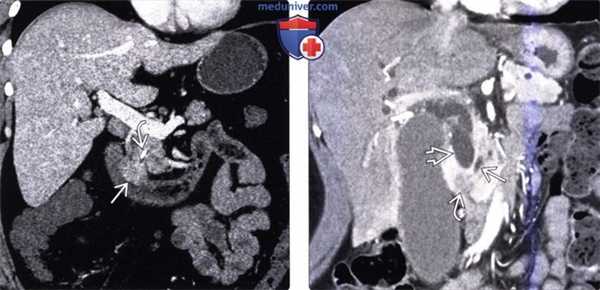

(Слева) На рисунке показан рак ампулы фатерова сосочка, приводящий к обструкции общего желчного и панкреатического протоков.

(Справа) На рентгенограмме (ЭРХПГ) у пациента, страдающего семейным полипозом, визуализируется небольшое объемное образование, вызывающее обструкцию общего желчного протока в области ампулы фатерова сосочка. Риск возникновения рака ампулы фатерова сосочка, а также рака другой локализации у пациентов, страдающих семейным полипозом, в значительной степени повышен. В таких случаях для выявления опухолей кишечника, желудка и билиарной системы необходимо пожизненное наблюдение. (Слева) На корональной КТ с контрастным усилением определяется классический симптом «двойного протока», обусловленный раком ампулы фатерова сосочка, приводящим к обструкции общего желчного и панкреатического протоков. Обратите внимание на внезапный «обрыв» этих протоков возле опухоли.

(Справа) На корональной КТ с контрастным усилением визуализируется объемное образование с бугристыми краями, расположенное в ампуле фатерова сосочка, приводящее к обструкции панкреатического и общего желчного протоков. Лучевые методы не дают возможности дифференцировать опухоли различного типа: в этом случае при гистологическом исследовании была обнаружена опухоль панкреатобилиарного типа.

(Слева) На корональной КТ с контрастным усилением визуализируется полиповидное объемное образование (рак) в ампуле фатерова сосочка. Видна также часть билиарного стента ЕЕ. Изображения в корональной плоскости лучше всего позволяют визуализировать ампулу и оценить вероятное объемное образование.

(Справа) На корональной КТ с контрастным усилением визуализируется гиподенсное образование в ампуле, с нечеткими краями, вызывающие обструкцию общего желчного протока, при этом панкреатический проток расширен в незначительной степени. При оперативном вмешательстве был обнаружен рак ампулы фатерова сосочка.